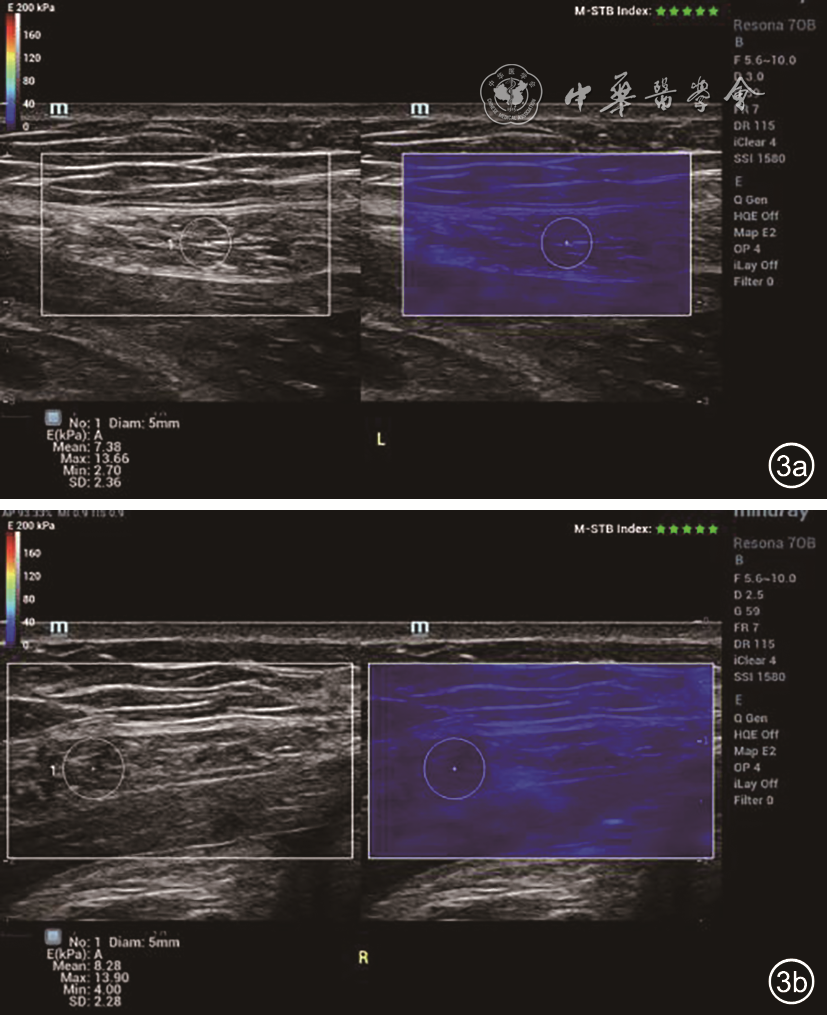

2. 方法:受检者平躺,暴露腹部检查区域,采用横向、纵向、斜向多平面结合方式先进行实时二维灰阶扫查,观察剑突以下至耻骨联合以上的腹直肌情况,测量脐水平、脐上5 cm水平、脐下5 cm水平的双侧腹直肌高回声筋膜内侧缘间的距离,记录为IRD0、IRD+5、IRD-5图12)。二维超声定位双侧腹直肌内侧1~2 cm范围内的部位,嘱患者屏气3~5 s,开启SWE扫查模式,剪切波弹性的量程为0~180 kPa,待图像稳定后冻结,选择感兴趣区域(region of interest,ROI),ROI范围为双侧腹直肌内侧1~2 cm的最大测量面积(不包括腹直肌筋膜),手持探头在检测部位,不施加压力。双幅实时显示功能观察二维图与弹性图,选取ROI,静置3~5 s,保持探头稳定以获得稳定弹性图(M-STB Index:5颗绿星)并保存,观察和记录该区域弹性模量颜色分布特征。仪器自带Q-BOXTM定量测量工具,测量ROI范围内杨氏弹性模量值[平均值(Emean)、最大值(Emax)、最小值(Emin)],每个区域(右侧腹直肌脐水平R0、左侧腹直肌脐水平L0、右侧腹直肌脐上5 cm水平R+5、左侧腹直肌脐上5 cm水平L+5、右侧腹直肌脐下5 cm水平R-5、左侧腹直肌脐下5 cm水平L-5)中部水平测量2次,取平均值(图34)。

图3 22岁未育女性,脐上5 cm水平左侧腹直肌剪切波弹性成像(SWE)定量测量,Emean=7.38 kPa,Emax=13.66 kPa,Emin=2.70 kPa(图a);右侧腹直肌SWE定量测量,Emean=8.28 kPa,Emax=13.9 kPa,Emin=4.0 kPa(图b)